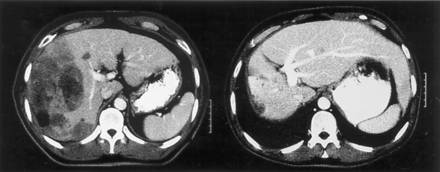

CT scan of unresectable hepatocellular carcinoma durable response 11 months after focal liver RT and hepatic arterial FUdR

PURPOSE: To evaluate the response, time to progression, survival, and impact of radiation (RT) dose on survival in patients with intrahepatic malignancies treated on a phase I trial of escalated focal liver RT. PATIENTS AND METHODS: From April 1996 to January 1998, 43 patients with unresectable intrahepatic hepatobiliary cancer (HB; 27 patients) and colorectal liver metastases (LM; 16 patients) were treated with high-dose conformal RT. The median tumor size was 10 x 10 x 8 cm. The median RT dose was 58.5 Gy (range, 28.5 to 90 Gy), 1.5 Gy twice daily, with concurrent continuous-infusion hepatic arterial fluorodeoxyuridine (0.2 mg/kg/d) during the first 4 weeks of RT. RESULTS: The response rate in 25 assessable patients was 68% (16 partial and one complete response). With a median potential follow-up period of 26.5 months, the median times to progression for all tumors, LM, and HB were 6, 8, and 3 months, respectively. The median survival times of all patients, patients with LM, and patients with HB were 16, 18, and 11 months, respectively. On multivariate analyses, escalated RT dose was independently associated with improved progression-free and overall survival. The median survival of patients treated with 70 Gy or more has not yet been reached (16.4+ months), compared with 11.6 months in patients treated with lower RT doses (P =.0003). CONCLUSION: The excellent response rate, prolonged intrahepatic control, and improved survival in patients treated with RT doses of 70 Gy or more motivate continuation of dose-escalation studies for patients with intrahepatic malignancies.